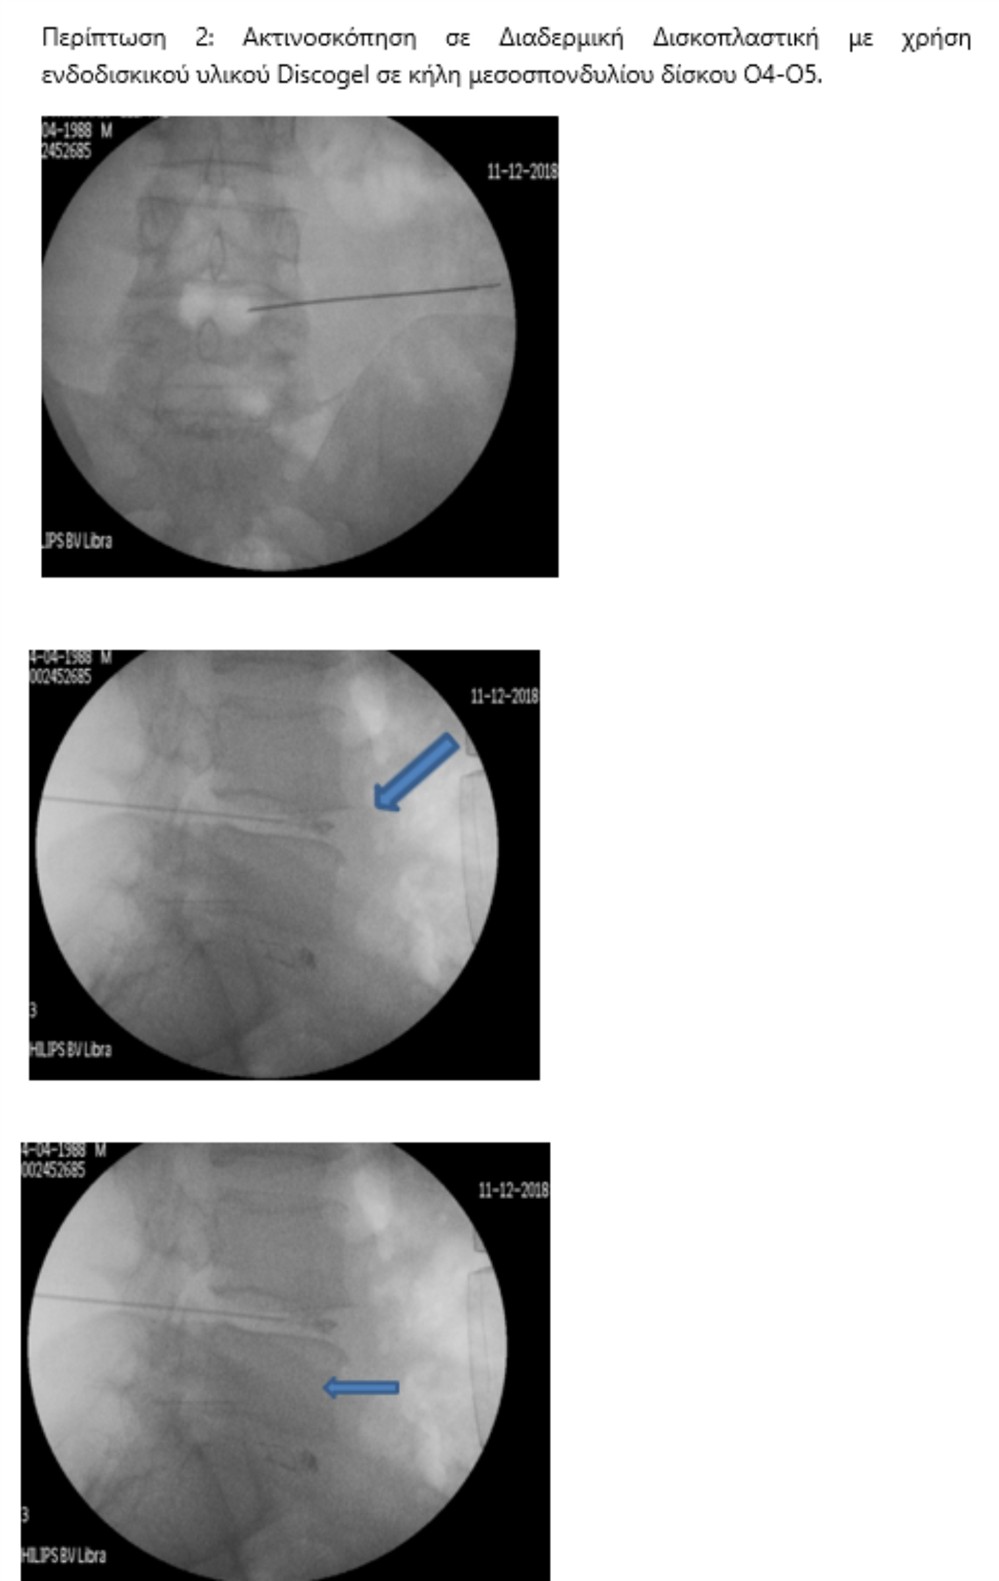

Αναλυτικότερα, υπάρχουν δύο τρόποι εφαρμογής της. Ο πρώτος τρόπος αφορά τη χρήση τεχνολογίας ραδιοσυχνοτήτων και ο δεύτερος τρόπος εκτελείται με έγχυση ενδοδισκικού υλικού σε μορφή gel (Discogel).